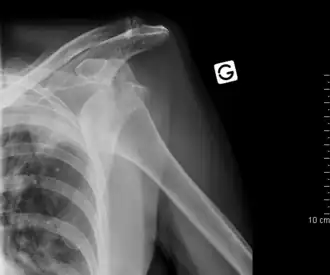

Luxation antérieure sous-coracoïdienne de l'épaule gauche.

Luxation de l'épaule ou scapulo-humérale

La luxation scapulo-humérale ou gléno-humérale, le plus souvent antérieure « pure » mais peut s'accompagner d'une fracture de la grande tubérosité (ou trochiter) dans ce cas la réduction est la même, mais il faudra fixer le fragment au reste de l'humérus. Quand il n'y a pas d'arrachement osseux, la réduction doit être rapidement réalisée, pas tant pour l'avenir de l'articulation mais plutôt pour la moindre difficulté de réalisation. En effet de nombreuses techniques ont été décrites, la plus connue est celle d'Hippocrate, consistant à tirer sur le bras dans l'axe en plaçant le pied de l'opérateur dans l'aisselle du patient. Cette technique se heurte à de nombreux échecs car source de douleurs importantes, or la réussite d'une réduction dépend directement du relâchement musculaire du patient. Ceci explique la variabilité individuelle, certaines luxations de l'épaule se résolvant sans aucune anesthésie, ni sédation, simplement avec une analgésie légère, et d'autre se terminant au bloc opératoire sous anesthésie générale après plusieurs tentatives infructueuses (en particulier chez un sujet jeune et musclé pour lequel le relâchement musculaire n'a pas pu être obtenu). De toutes façons la réduction est un geste médico-chirurgical, les risques sont la blessure du nerf circonflexe qui détermine la sensibilité du galbe de l'épaule, il peut être abimé au moment du traumatisme comme lors du traitement et sa blessure doit être recherchée et consignée sur le dossier médical. Les autres blessures sont plus rares, signalons juste le risque de fracture de la tête humérale sur le bord de l'omoplate chez un patient âgé à os fragile. Tout ceci est valable pour la luxation en avant de l'omoplate mais il existe des luxations postérieures, donc en arrière de diagnostic plus difficile (pouvant être une lésion traumatique suivant une crise d'épilepsie), et des luxations inférieures "erecta", le bras restant levé vers le ciel sans possibilité d'abaissement. Le déplacement étant particulier, la réduction nécessite toujours une anesthésie générale. Les luxations répétées ou itératives ne guériront plus et nécessiteront une stabilisation chirurgicale pour éviter les récidives.